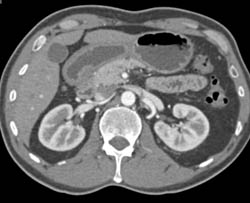

Diagnosis

Linitis Plastica